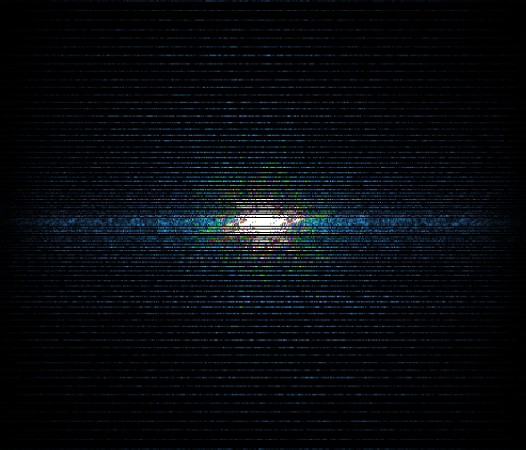

In the example below, only one fifth of the required MR radiofrequency signals is recorded. This results in a five times faster acquisition, with a subsampled k-space (top left) and inherent image artifacts after standard reconstruction (top right).

K space

The Compressed SENSE reconstruction then uses iterative, knowledge-based algorithms to fill in the empty lines in k-space (bottom left). This removes the artifacts while keeping the final image fully consistent with the acquired data (bottom right).